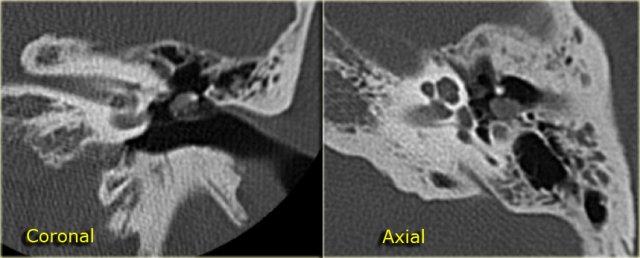

Bên trái là hình ảnh của một bé gái 2 tuổi.

Các hình ảnh từ kết quả chụp CT được thực hiện trước khi cấy ốc tai điện tử.

Quan sát thấy dị dạng nhẹ ở đỉnh ốc tai – không có sự phân tách giữa vòng thứ hai và vòng thứ ba, và trụ ốc tai xương vắng mặt.

Cống tiền đình bình thường.